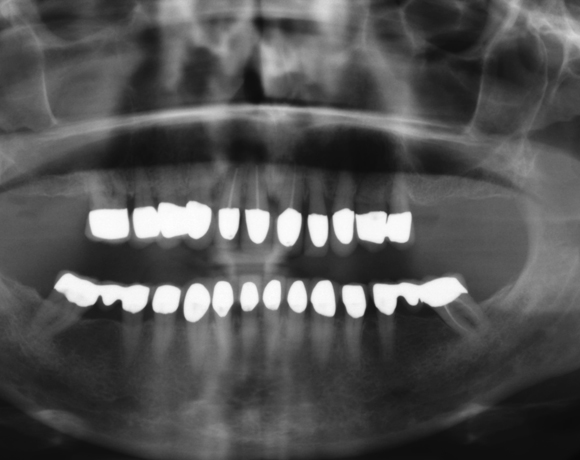

Der vorliegende Patientenfall zeigt eine komplette Neuversorgung der vorhandenen Metallkeramikkronen mit vollkeramischen Restaurationen. Zusätzlich wurde im Oberkiefer die Zahnreihe mit zwei Implantaten, für die fehlenden Molaren, ergänzt. Da keine ausreichende Knochenhöhe vorhanden war wurde ein interner Sinuslift geplant.